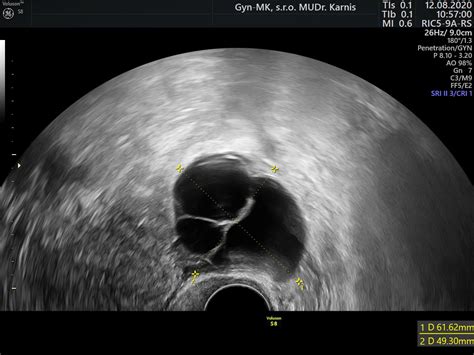

Počas hormonálnej stimulácie, ktorá trvá jeden až tri týždne, sa pomocou ultrazvukových kontrol sleduje rast folikulov, aby sa stanovil optimálny čas na odber vajíčok. Keď sú podmienky ideálne, pomocou injekcií hCG (ľudský choriový gonadotropín) sa vyvolá ovulácia.

Monitoring predstavuje pravidelné kontroly zamerané na sledovanie rastu a dozrievania folikulov (vačkov s vajíčkami) v hormonálne stimulovanom cykle. Monitorovanie prebieha formou:

- Ultrazvukovej folikulometrie: Meria sa počet a veľkosť folikulov.

Na základe výsledkov hormonálneho profilu, AMH a veku ženy sa volí vhodný stimulačný protokol (dlhý alebo krátky) a kombinácia stimulačných preparátov. Počas stimulácie absolvujete niekoľko kontrol v centre (zvyčajne 2 - 4), kde sa ultrazvukom kontroluje odpoveď vaječníkov na stimuláciu a sledujú sa hormonálne ukazovatele z krvi.